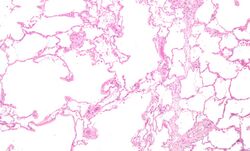

![]() | |

| Section of a lung showing centrilobular emphysema, with enlarged airspaces in the centre of a lobule usually caused by smoking and a major feature of COPD | |